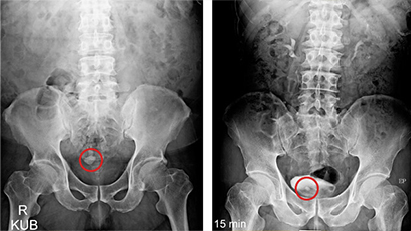

01방사선 검사는 X-ray 촬영을 통해 신장, 요관, 방광을 검사합니다.

02초음파 검사는 초음파 검사기를 통해 혈뇨를 검사합니다.

방광결석